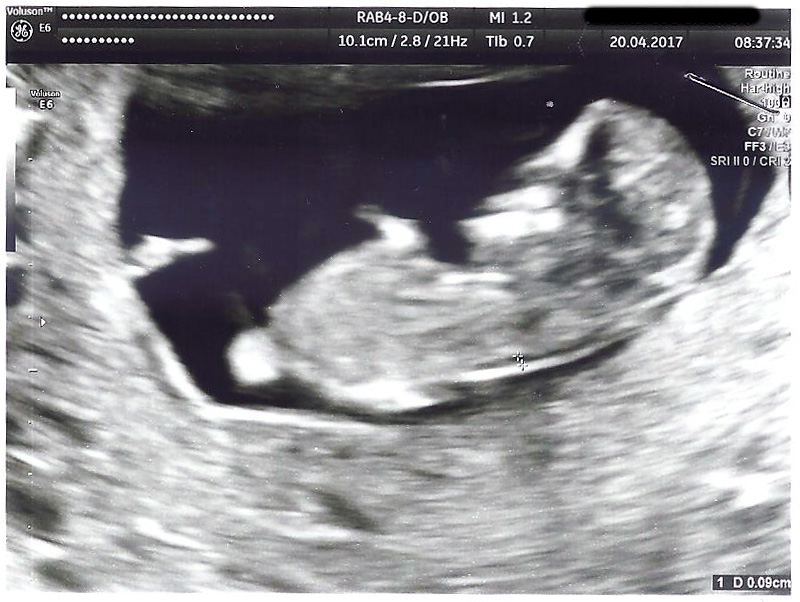

Any predictions based on Ramzi or nub theory? Thanks!

Attachment 35892

Looks like a boy to me :)

Early but boyish [emoji170]